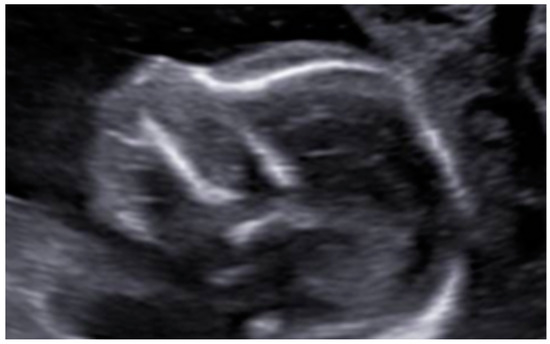

3. Results: Case Presentation